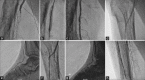

Figure 8

PTA of combined right superficial femoral artery and right infrapopliteal artery occlusion through ipsilateral common femoral artery puncture. (a) Demonstration of superficial femoral artery occlusion. (b) Balloon dilatation of superficial femoral artery lesion. (c) Final result of superficial femoral artery lesion after balloon angioplasty. (d and e) Crossing the infrapopliteal artery lesion by Terumo wire. (f-h) Final result of infrapopliteal artery lesion after balloon dilatation